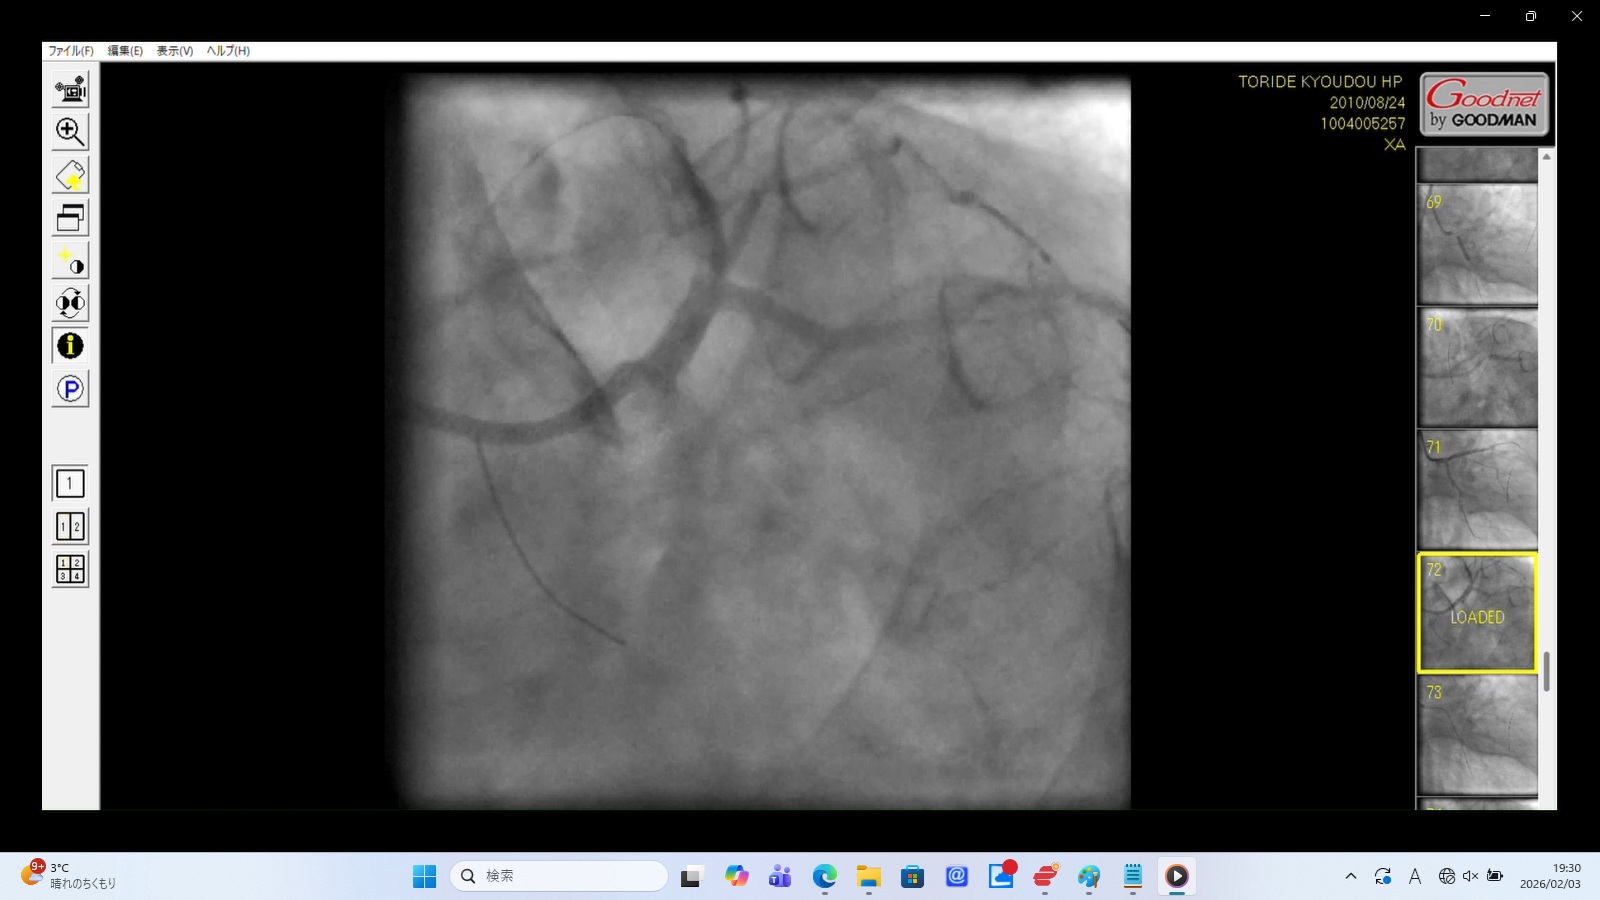

6. XA0072.mp4:左冠動脈前下行枝(LAD)の穿孔・解離(画像をクリックすると動画再生)

画像データ:SHA256:A9A15799FED7D203A799A709908B27FD2498D43DEB263C0DD43BF6BCD78925B4

これらは冠動脈穿孔の典型的な所見。

カテーテル/ワイヤーの逸脱: XA0072.mp4では、ガイドワイヤーの先端がLADの本来の走行に超えて、心臓の辺縁部まで突き抜けている。

造影剤の漏出: 画像の下の方がやや黒く染まっており、血管外に漏出した造影剤が下の方に貯留している。これは血管壁が破れ、心嚢内へ血液と造影剤が漏れ出している決定的な証拠。

血流の途絶: 左冠動脈主幹部入口部で造影剤が跳ね返されるのは、左冠動脈主幹部解離・損傷に伴う閉塞を示す重大な所見。